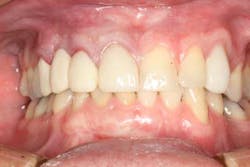

One year post-insertion radiographs indicate that bone levels around the implant remain stable. Clinical results 1.5 years post-insertion reveal gingival levels to be stable and healthy, and the patient is very pleased with the esthetic result of his treatment.